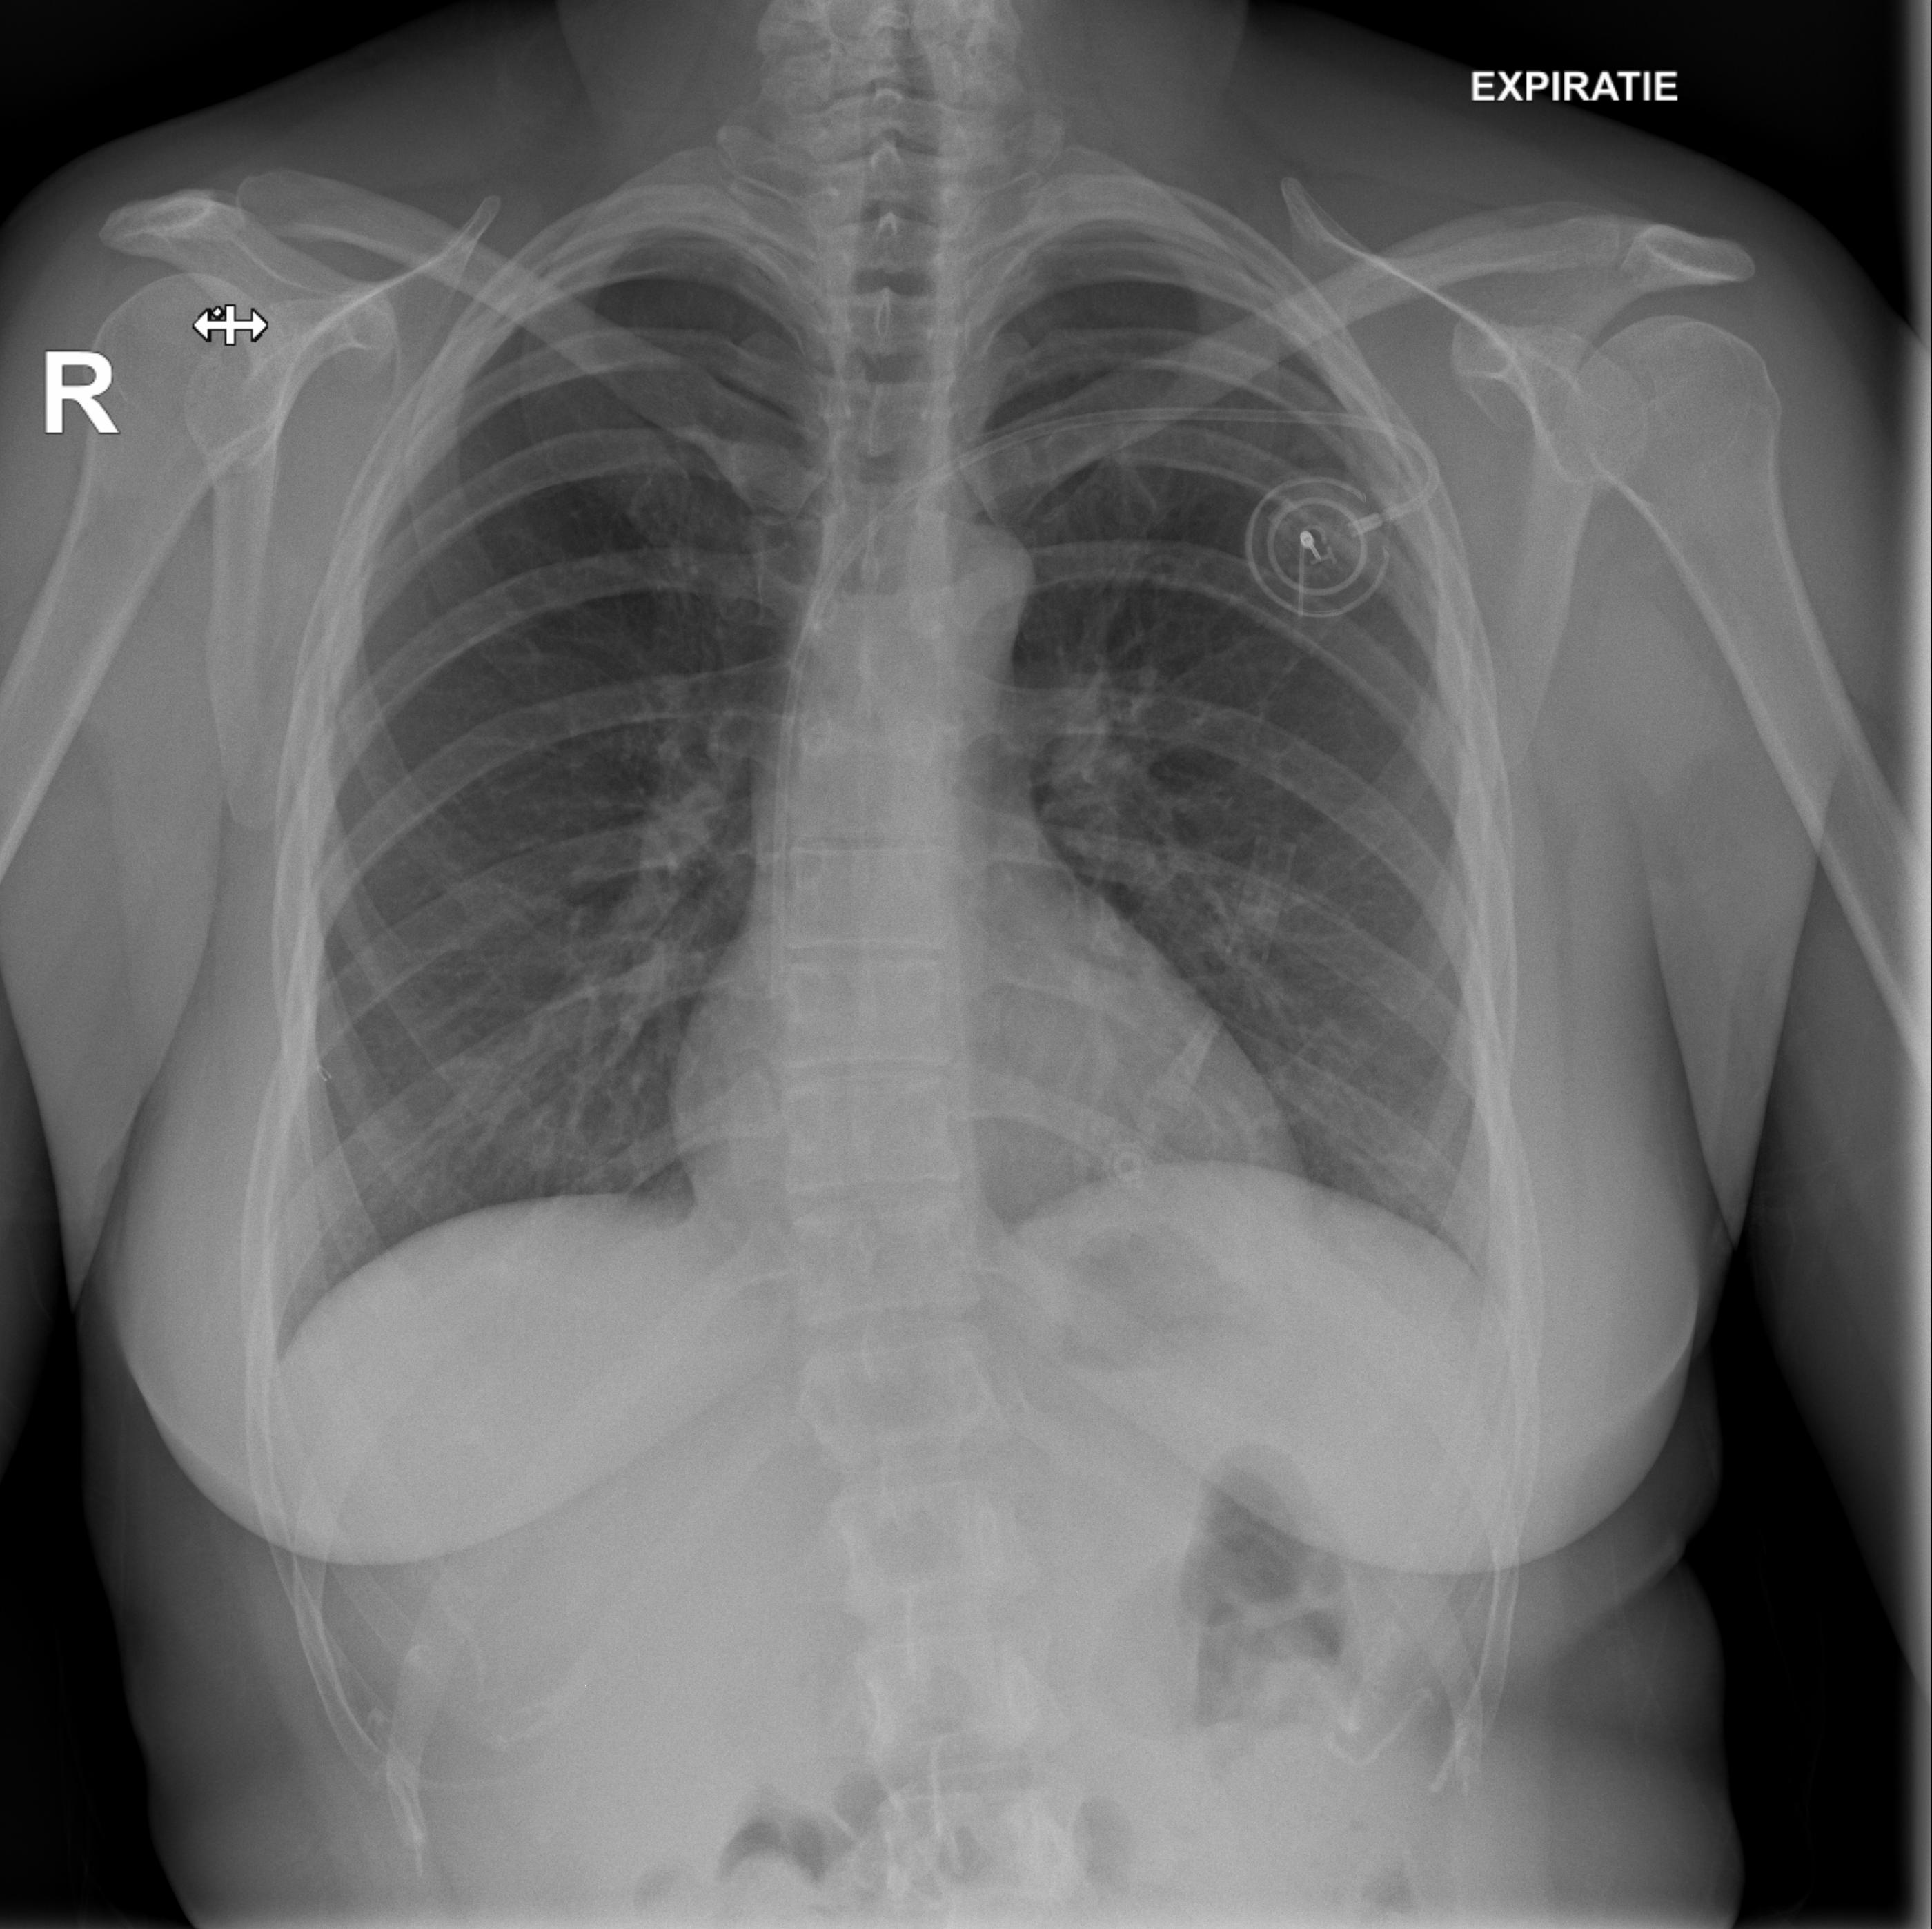

Chemotherapy day (finally) arrived: the sooner I started, the better, obviously. Not sure what happened on the day, but I fainted while getting ready. The pain from the port surgery, the tiredness, the stress of it all, I just went down on my face. My oncologist suspected a pneumothorax (a collection of air outside the lung but within the pleural cavity) so I was sent to radiology for some x-rays.

They checked my lungs during inspiration (first image) and expiration (second image): you can clearly see Portia with the catheter getting into my subclavian vein.

Luckly enough, I didn’t have a pneumothorax, so we went ahead with chemotherapy.